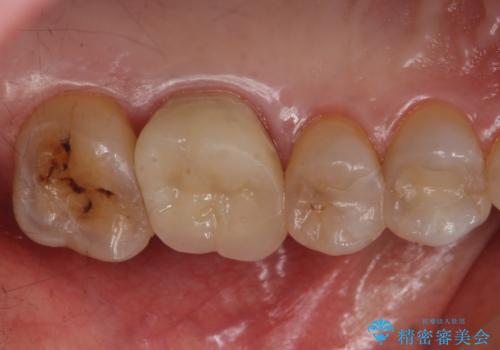

虫歯を取りきった後セラミッククラウンでの修復処置を行います。

今回は過去に治療された部分をすべてやり直しました。

再治療にならないような精密な治療が重要です。